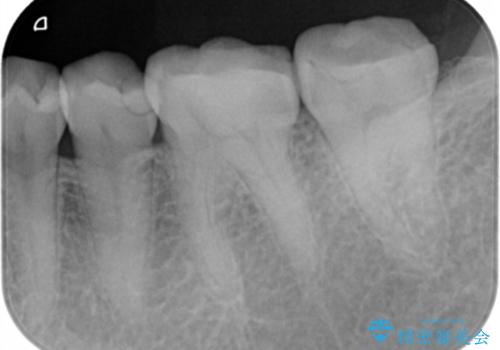

- 歯が黒くて虫歯じゃないかと心配して来院。

過去にプラスチックの樹脂で治療されており、歯とプラスチックの隙間から虫歯が進行していました。

拡大鏡下で虫歯を除去し、詰め物にて治療しました。

一番奥の歯は歯の高さが足りない、噛む面を覆う面が広くなってしまい、セラミックの詰め物だと割れるリスクが高くなってしまうので手前はセラミックインレー奥の歯はゴールドインレーにて治療しました。